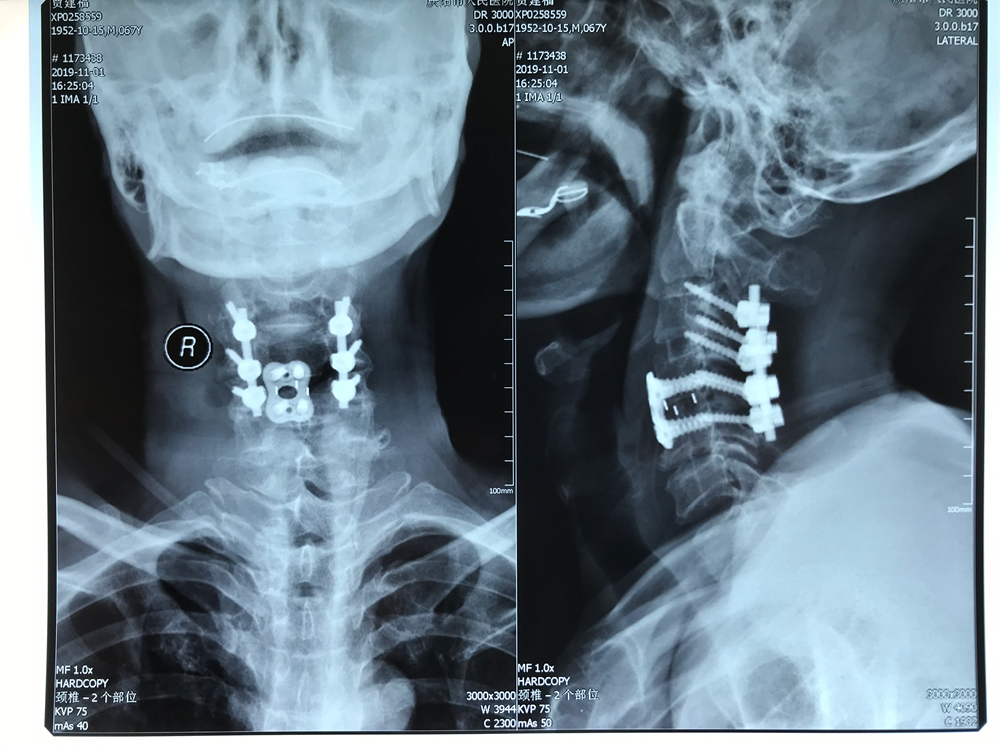

在骨一科醫(yī)護(hù)團(tuán)隊及麻醉手術(shù)配合下,手術(shù)歷時4小時,患者轉(zhuǎn)危為安。經(jīng)過康復(fù)訓(xùn)練,患者出院時可以自主下床活動、自主進(jìn)食及解大小便,生活質(zhì)量得到保證。

此例手術(shù)是我市骨科成功實(shí)施的首例一期完成頸前后聯(lián)合入路頸椎椎體完全性滑脫并椎體骨折內(nèi)固定術(shù)。該患者骨折的部位屬于高位脊髓水平,緊鄰呼吸循環(huán)等生命中樞,手術(shù)中稍有不慎,就會引起高位肢體癱瘓甚至死亡,過去往往被認(rèn)為是“手術(shù)的禁區(qū)”。此類患者多數(shù)在受傷當(dāng)時即出現(xiàn)危及生命的嚴(yán)重?fù)p傷,現(xiàn)場死亡率高,手術(shù)處理較為棘手,一般出現(xiàn)在嚴(yán)重車禍傷、高處墜落傷等情況下,要完成此類高難度、高風(fēng)險的手術(shù),要求手術(shù)團(tuán)隊有專業(yè)的理論知識、完善的術(shù)前準(zhǔn)備和精準(zhǔn)的手術(shù)操作。此例手術(shù)的成功,標(biāo)志著我院骨一科脊柱外科事業(yè)發(fā)展步入了一個新的臺階。